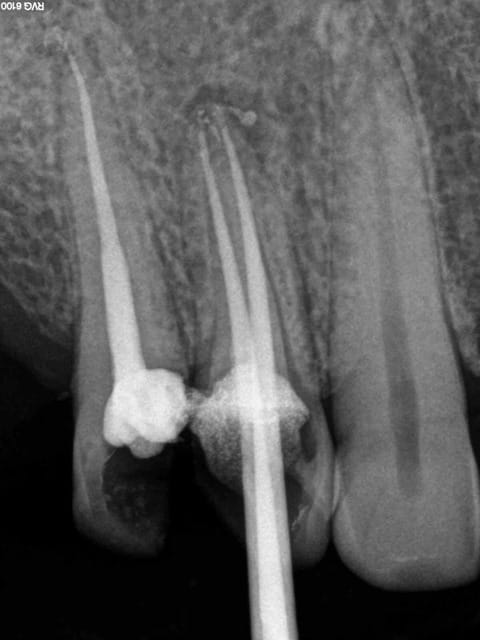

Aujourd'hui patient en urgence ca tombe bien pour une fois synchro avec un lapin.

45 mn de turbinage intensif 2 endos + 2 SC 33; On cote comment les radios ?

Z6, SC 20, Z3,Z3, SC20, Z3, Z3, SC 33, Z3, SC 33, Z3 ?